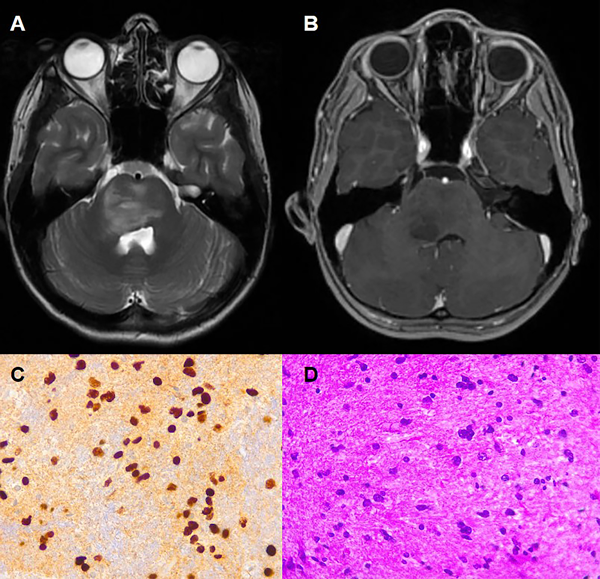

Una paciente femenina de 12 años, sin antecedentes de relevancia, que consulta por parálisis facial derecha y déficit motor braquiocrural izquierdo (Sindrome de Millard-Gubler). Se realizó una RMN de cerebro con contraste donde se evidencia lesión protuberancial expansiva, con componente exofítico, presentando extensión al pedúnculo cerebral derecho y región paramedial derecha del bulbo, y condicionando efecto de masa sobre el receso lateral derecho del IV° ventrículo, sin refuerzo con contraste EV. (Fig 3A-B). RMN de columna completa sin hallazgos patológicos.

Se decidió en conjunto con el equipo de oncología realizar la biopsia quirúrgica mediante un abordaje subtemporal, de la cual se enviaron 4 fragmentos de aproximadamente 0.5 cm x 1 cm. La anatomía patológica concluyó glioma difuso de la línea media H3 K27-alterado (grado 4 de la OMS). (Fig. 3C-D). La paciente cursó 2 días de internación en unidad de terapia intensiva con posterior traslado a sala general donde se otorgó el egreso sanatorial al cuarto día postoperatorio, sin presentar complicaciones. La paciente realizó radioterapia y se encuentra en seguimiento por oncología. (Fig. 4A-B).

Fig 3: Caso 2: RMN prequirúrgica (secuencias T2 (A) y T1 con contraste (B). Evidencian una lesión exofítica difusa a nivel de la protuberancia, con extensión al pedúnculo cerebral derecho. Sin franco realce con contraste EV. C y D representan las tinciones histológicas de las muestras quirúrgicas tumorales con H3 (C) y hematoxilina-eosina (D).